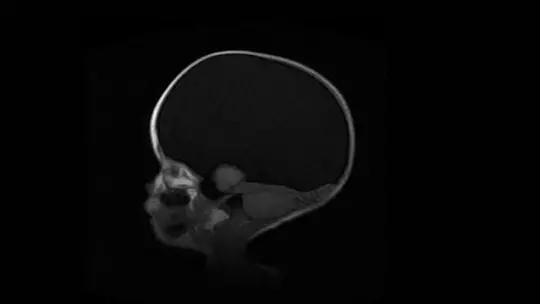

Macrocephaly is a biological alteration by which the circumference of the head is greater than expected for sex and age of a boy or girl. That is, the identification of macrocephaly is carried out by taking measurements of the perimeter of the skull and checking whether the cranial vault is larger than normal in healthy people. For this reason, macrocephaly is included within cranial growth disorders, a category to which microcephaly also belongs.

For example, many cases of macrocephaly are due to a disorder known as hydrocephalus in which more cerebrospinal fluid (a substance that surrounds the brain and spinal cord) is produced than can fit inside the skull. This means that in the first months of life the walls of the skull are more “dilated” than normal to accommodate so much fluid, given that at this vital stage the head is much less hard than in adulthood.

In this type of macrocephaly, the enlargement of the skull is due to biological processes that are not due to an increase in the brain itself but from other related substances that occupy head space. For example, hydrocephalus produces this variant.

Some cases of macrocephaly are explained by abnormal bone development. For example, they may be due to premature closure of the cranial sutures, which produces a bulging caused by the abnormal development of the nervous system produced by the chain reaction of not having space to expand at a given time.